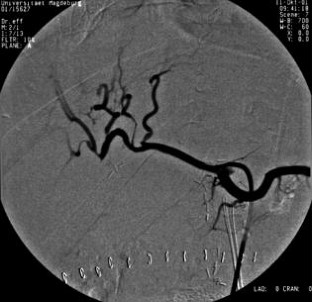

Wir berichten über das diagnostische und therapeutische Vorgehen anhand von 7 Patienten mit Blutungen aus der A. gastroduodenalis (n=5) nach pankreaschirurgischen Interventionen bei Pankreaskopfkarzinom, Rezidiv eines Liposarkoms und chronischer Pankreatitis, der A. hepatica communis (n=1) bei chronischer Pankreatitis und der A. mesenterica superior (n=1) nach akuter Pankreatitis. Anhand von 4 Kasuistiken werden unsere Erfahrungen mit der Implantation von Stentgrafts (Hemobahn®-Prothesen) vermittelt. Den Vorteil der Stentgrafts sehen wir in der sofortigen Blutstillung bei fehlendem Kontakt der Endoprothese zu infiziertem Gewebe und Erhalt der Perfusion des abhängigen Organs. Unsere positiven Erfahrungen mit diesen interventionellen Therapieverfahren erfordern jedoch weitere klinische Untersuchungen, wobei im Mittelpunkt die Indikationen, die technische Erfolgsrate, die stentbedingten Komplikationen und die Langzeitverläufe stehen sollten.

Spontaneous or postoperative hemorrhage into the abdominal cavity due to inflammatory vessel arrosion represents an uncommon but menacing situation. According to the literature, such hemorrhage is associated with a lethality of nearly 2%. Therapeutical options include reoperation and interventional radiological techniques such as endovascular catheter techniques with stent graft implantation or the embolization of vessels. We report on the management of seven cases with hemorrhage either from the gastroduodenal artery (n=5) following pancreatic surgery for pancreatic carcinoma, liposarcoma, and chronic pancreatitis or from the common hepatic artery (n=1) and the superior mesenteric artery (n=1) following chronic pancreatitis. The present article describes our experiences with stent graft implantation (hemobahn prosthesis) in four cases. Based on these experiences, we see the advantages of stent grafts in primary hemostasis without any contact to infected tissue and the preservation of regular perfusion. However, further clinical data are required focussing on indication, technical success rates, stent-related complications, and long-term outcome.

Abb. 2